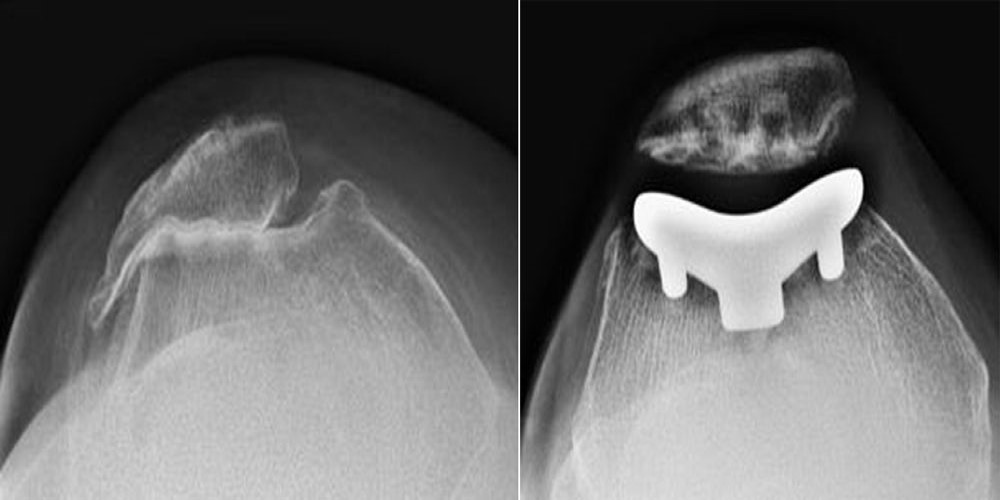

Patellofemoral Joint Replacement Kneecap Replacement Dr. Likover

Image by : www.drlikover.com